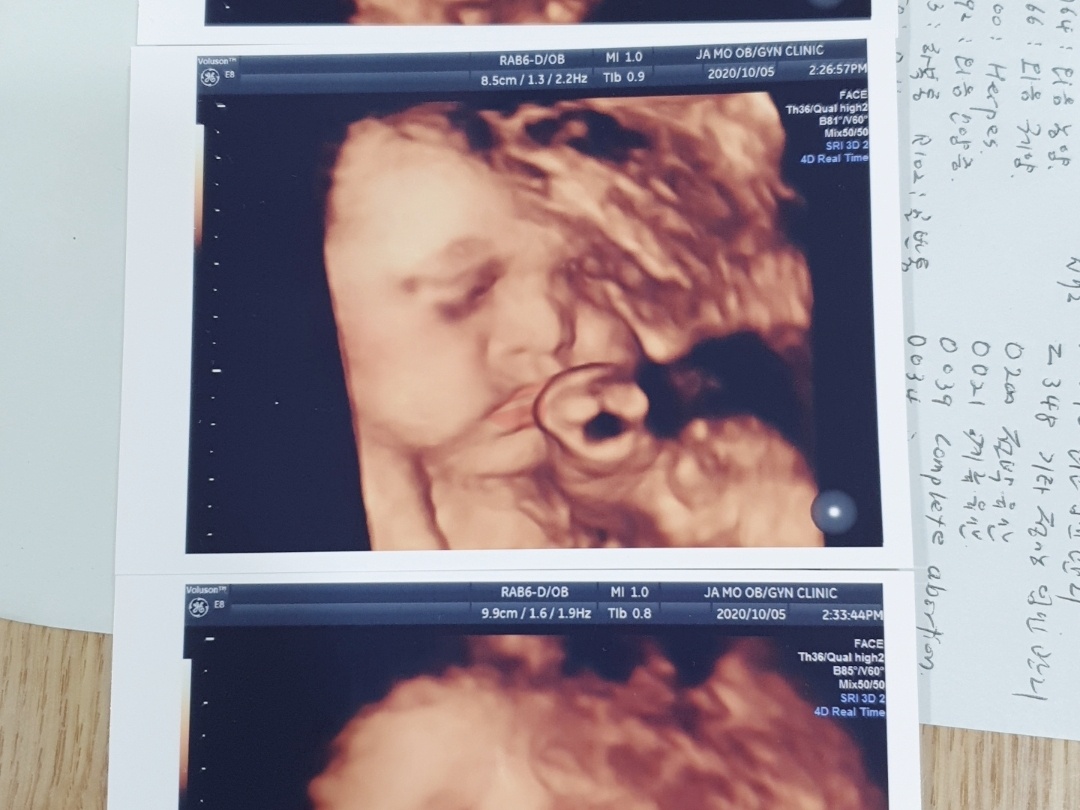

임신을 하면서 초기에는 격주로 한번, 중기, 후기로 가면 한 달에 한번 아기 초음파를 했습니다. 30주가 넘어가면 아기 영상 초음파까지 하게 되는데요. 그럴 때마다 초음파 동영상, 사진 자료를 받아오면 옆에 적혀있는 의학 약자 용어들이 많아요. 선생님이 설명해 주실 때 한번 듣긴 했지만 제대로 기억나지 않아 다시 봐도 약자가 어려워 의미를 알기 어렵더라고요. 그래서 제가 찾아 정리해 본 용어를 공유해 보겠습니다.